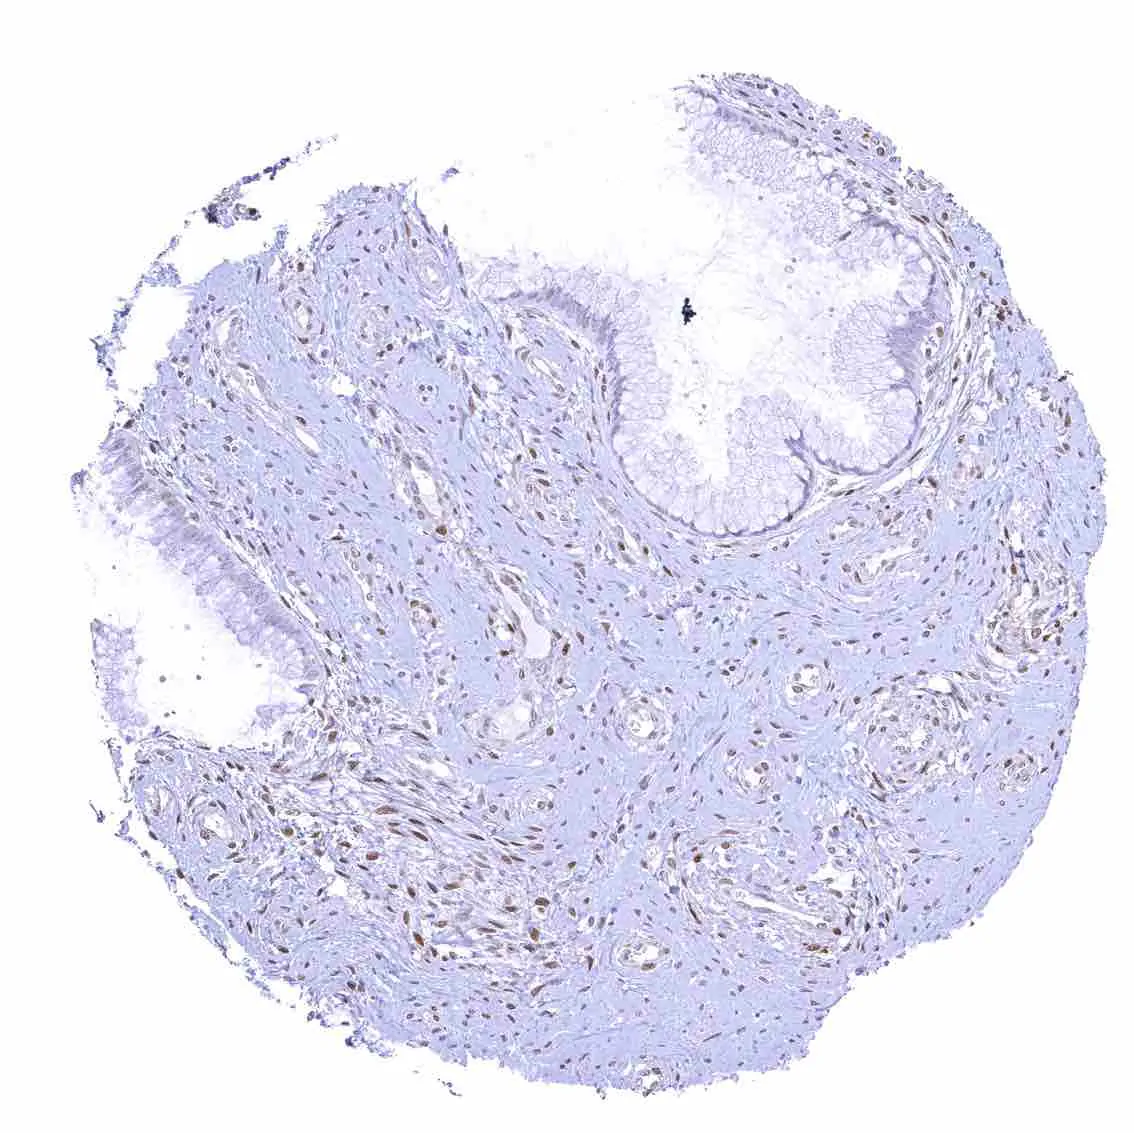

Esophagus, squamous epithelium – Nuclear staining of squamous epithelial cells predominates in the more mature cell layers (top 50_ of the epidermis).

Skin – Moderate to strong nuclear p27 staining occurs in a large fraction of squamous epithelial cells and predominates in the more mature cell layers (top 50_ of the epidermis).

Tonsil – Strong nuclear p27 staining of a significant subset of cells, especially in the interfollicular area. Nuclear staining of squamous epithelial cells predominates in the more mature cell layers (top 50_ of the epidermis).

Tonsil, surface epithelium – Strong nuclear p27 staining of a significant subset of cells, especially in the interfollicular area. Nuclear staining of squamous epithelial cells predominates in the more mature cell layers (top 50_ of the epidermis).

Uterus, ectocervix – Nuclear staining of squamous epithelial cells predominates in the more mature cell layers (top 50_ of the epidermis).